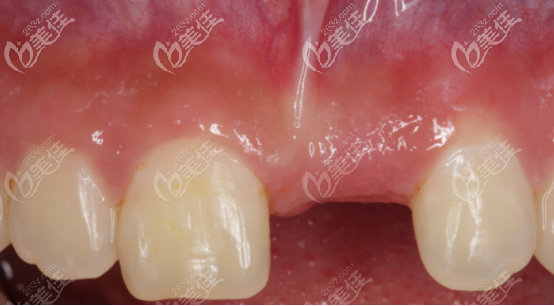

術前照片:

術前正面門牙照片,可以看出缺牙的位置骨量不足,而且中度凹陷。